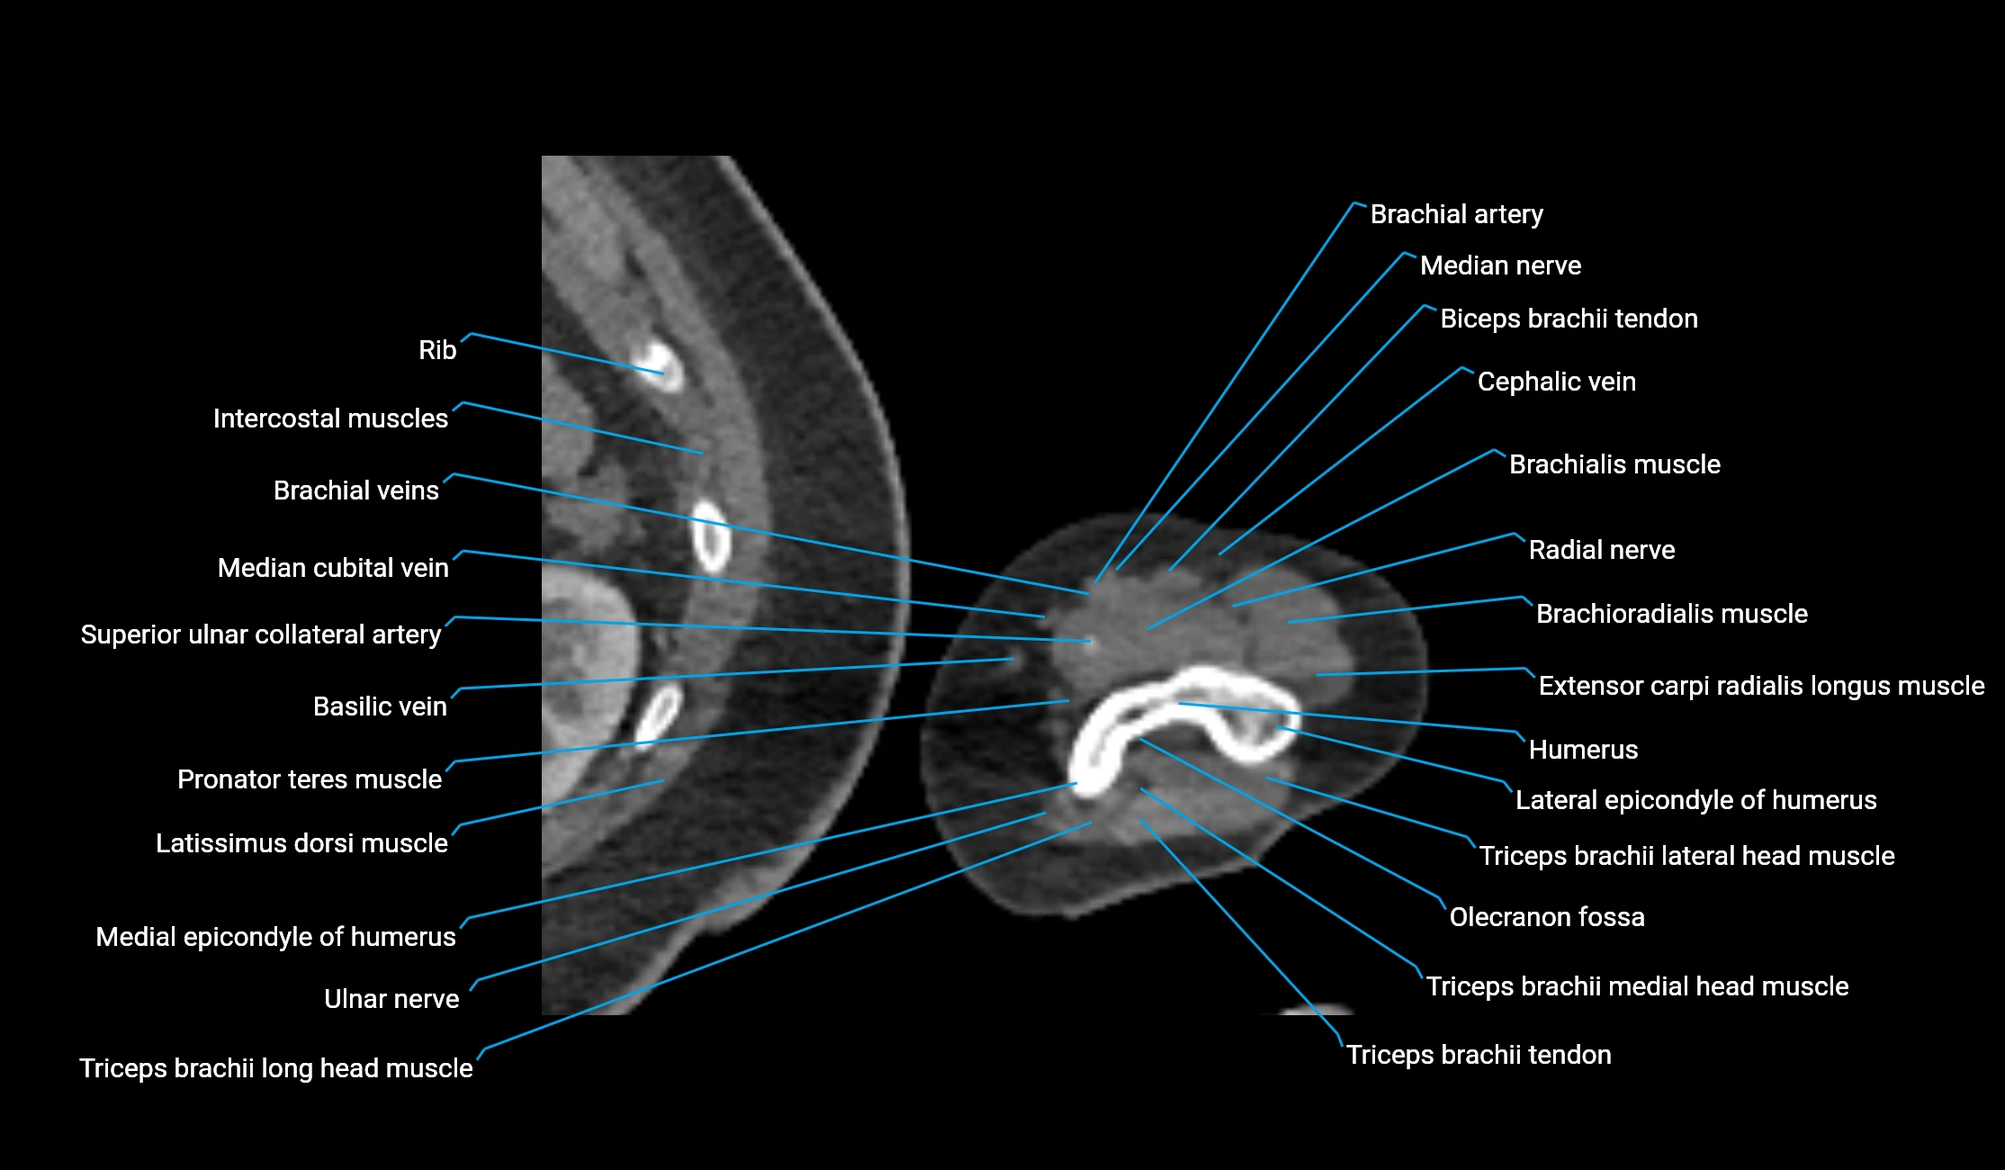

- Brachial artery

- Brachialis muscle

- Brachioradialis muscle

- Cephalic vein

- Extensor carpi radialis longus muscle

- Lateral epicondyle of humerus

- Lateral head of triceps brachii muscle

- Long head of triceps brachii muscle

- Medial epicondyle of humerus

- Medial head of triceps brachii muscle

- Median cubital vein

- Median nerve

- Olecranon fossa

- Radial nerve

- Superior ulnar collateral artery

- Triceps brachii tendon

- Ulnar nerve